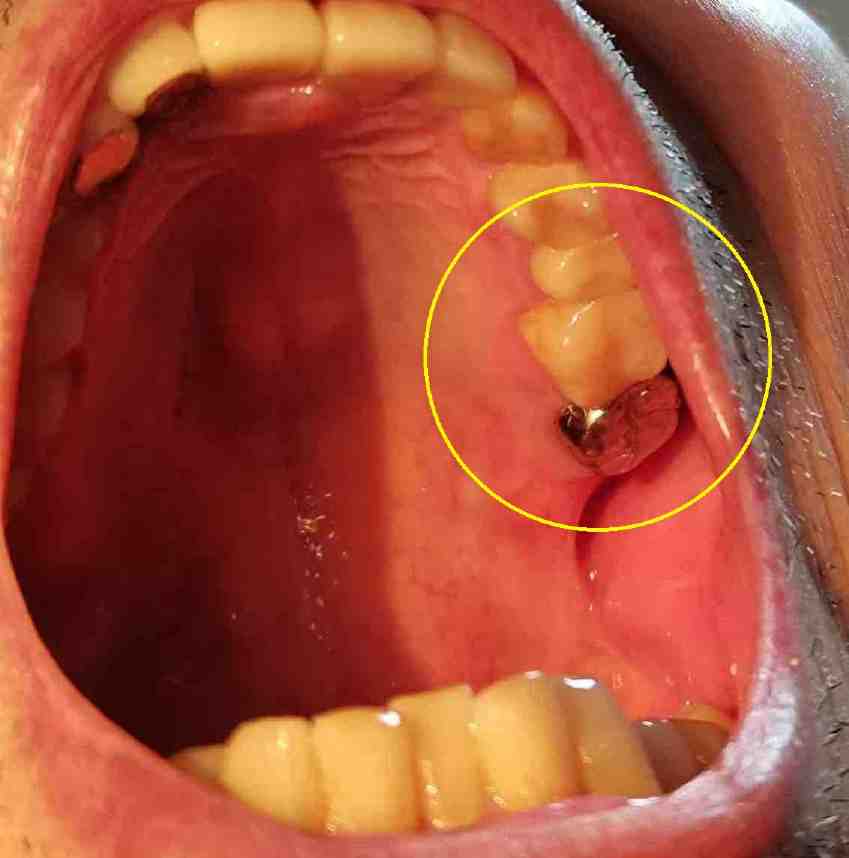

奥から2本目

虫歯の治療は 今日でおしまい

次回からは歯茎の治療、だそうな。